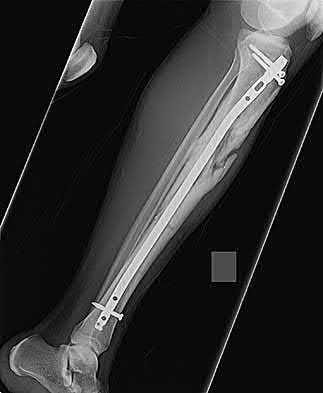

Which bone morphogenetic protein (BMP) is FDA-approved as an alternative to autograft for the treatment of acute, open tibial shaft fractures stabilized with an intramedullary nail?

Correct Answer: rhBMP-2

Explanation:

Recombinant human Bone Morphogenetic Protein-2 (rhBMP-2) is FDA approved for use in acute, open tibial shaft fractures stabilized with an intramedullary nail. rhBMP-7 (Osteogenic Protein-1 or OP-1) previously had a Humanitarian Device Exemption (HDE) for recalcitrant long bone nonunions but is no longer commercially available in the US for this indication.